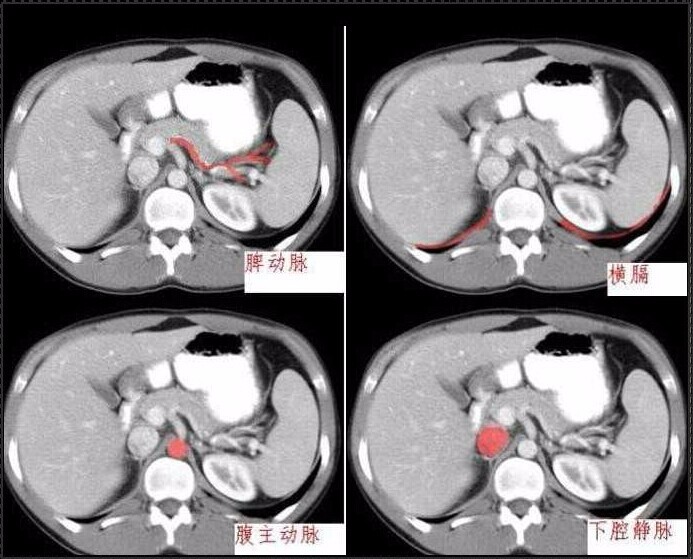

十分钟学会腹部CT解剖(多图)